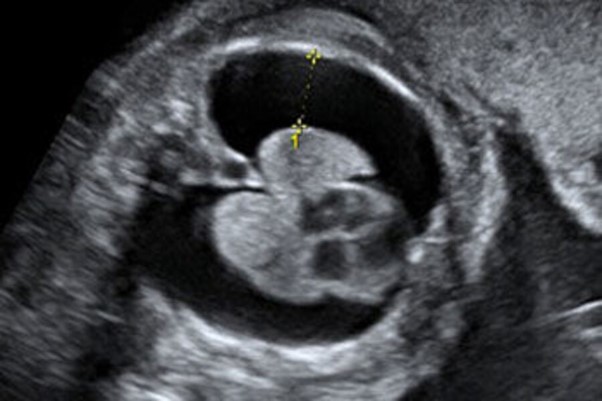

Trong những trường hợp dịch tích tụ nhiều, chọc hút dịch màng phổi thai nhi dưới hướng dẫn siêu âm được xem là biện pháp can thiệp quan trọng, giúp giảm chèn ép lồng ngực, hỗ trợ tuần hoàn và cải thiện cơ hội sống cho thai nhi.

Theo BSCKI. Vương Thị Bích Thủy - Bác sĩ Trung tâm Y học Bào thai, Bệnh viện Đại học Phenikaa (PhenikaaMec), chọc hút dịch màng phổi thai nhi dưới siêu âm là thủ thuật can thiệp bào thai nhằm dẫn lưu lượng dịch bất thường tích tụ trong khoang màng phổi. Thủ thuật được thực hiện bằng kim chuyên dụng, đi qua thành bụng mẹ, tử cung và tiếp cận khoang màng phổi thai nhi dưới sự hướng dẫn trực tiếp của siêu âm.

Việc theo dõi hình ảnh thời gian thực giúp bác sĩ kiểm soát chính xác vị trí kim, lượng dịch được hút ra và kịp thời điều chỉnh thao tác nếu phát hiện bất thường, từ đó hạn chế tối đa nguy cơ biến chứng cho cả mẹ và thai nhi. Can thiệp sớm trong tử cung giúp cải thiện chức năng phổi và tuần hoàn của thai.